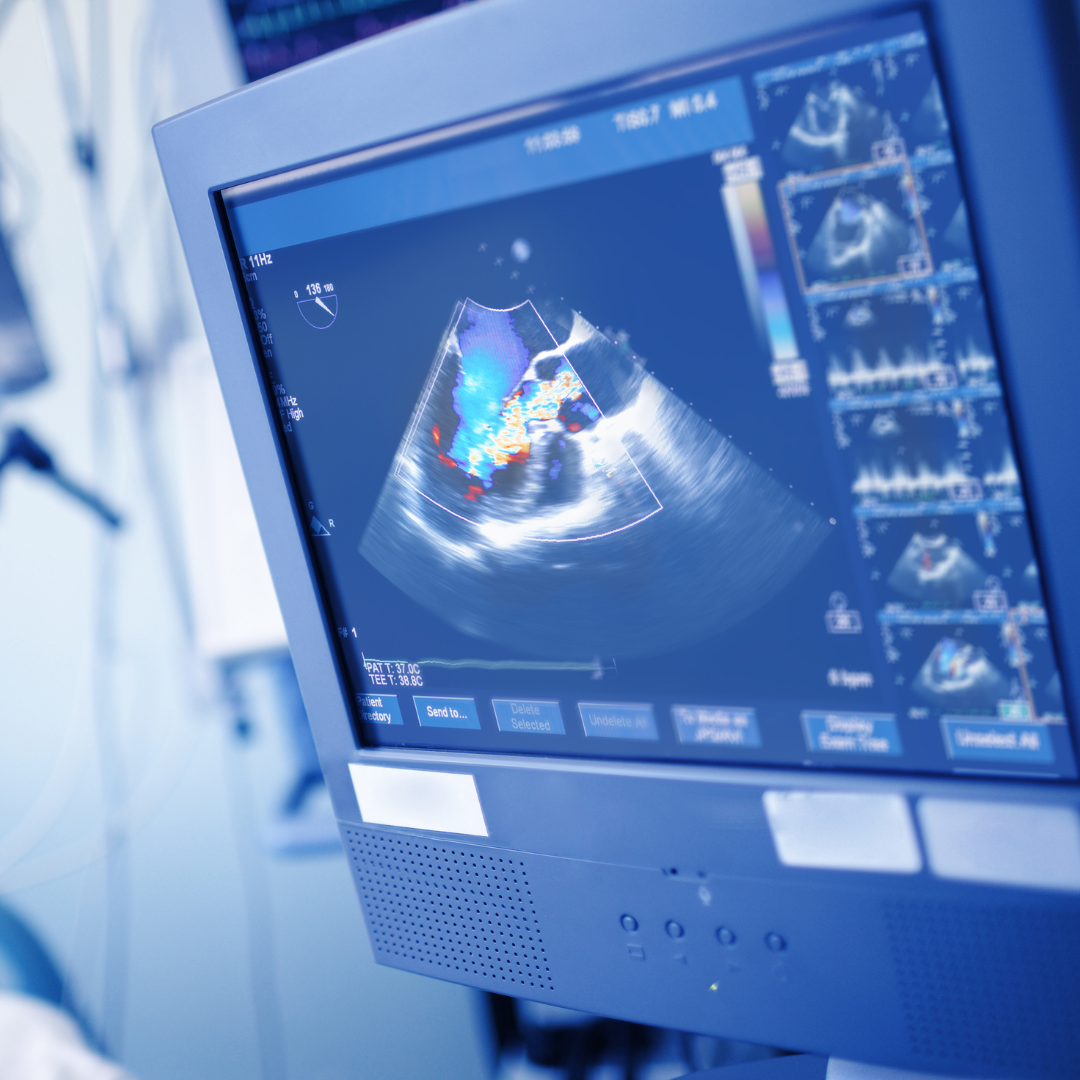

Echocardiography, commonly referred to as an “Echo,” is a non-invasive diagnostic test that uses ultrasound waves to create detailed images of the heart.

Transesophageal Echocardiography (TEE):

Involves inserting a probe into the esophagus to get clearer images of the heart.

Doppler Echocardiography:

Focuses on blood flow and pressure within the heart.